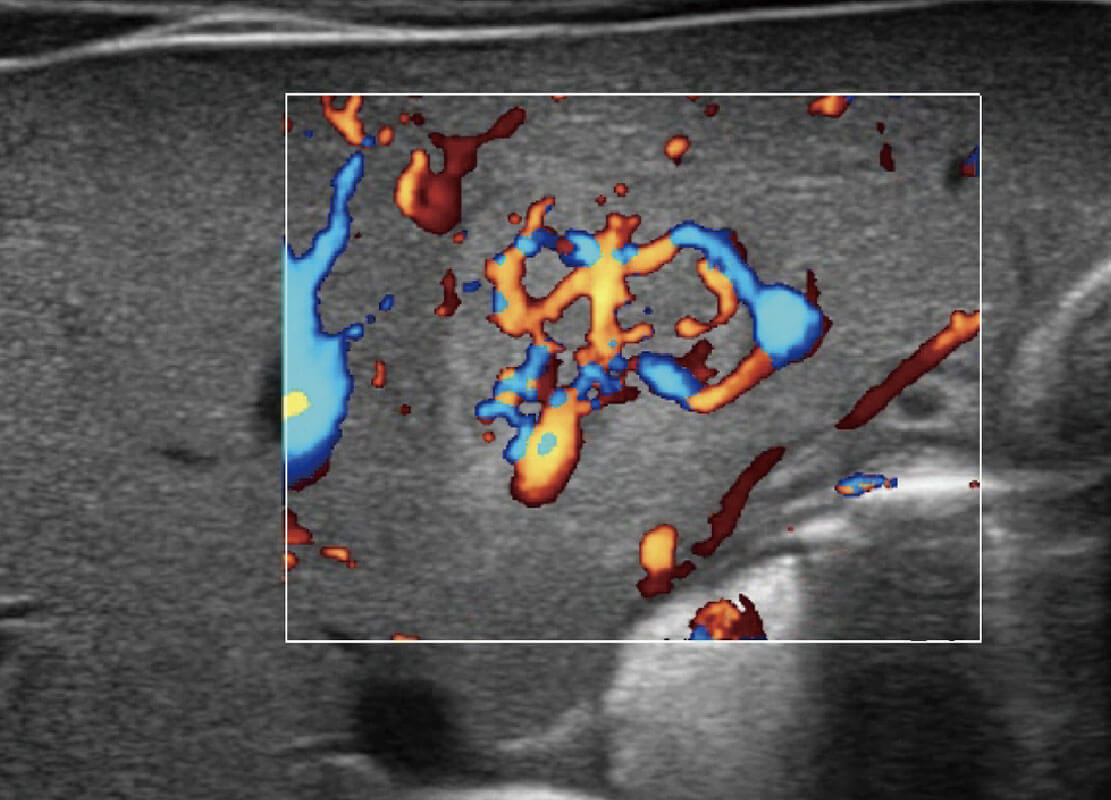

乳腺超声 / 新生儿

P60搭载宽频带线阵探头、宽景成像、弹性成像技术,为您提供乳腺应用方案。P60支持高频相控阵探头、线阵探头、腹部高频探头、腹部微凸探头等,丰富的探头群搭载敏感的彩色血流成像,适用于新生儿多种脏器检测要求,满足新生儿筛查需求。

• 乳腺导管癌

• 乳腺癌显微血流

• 新生儿肝血管癌